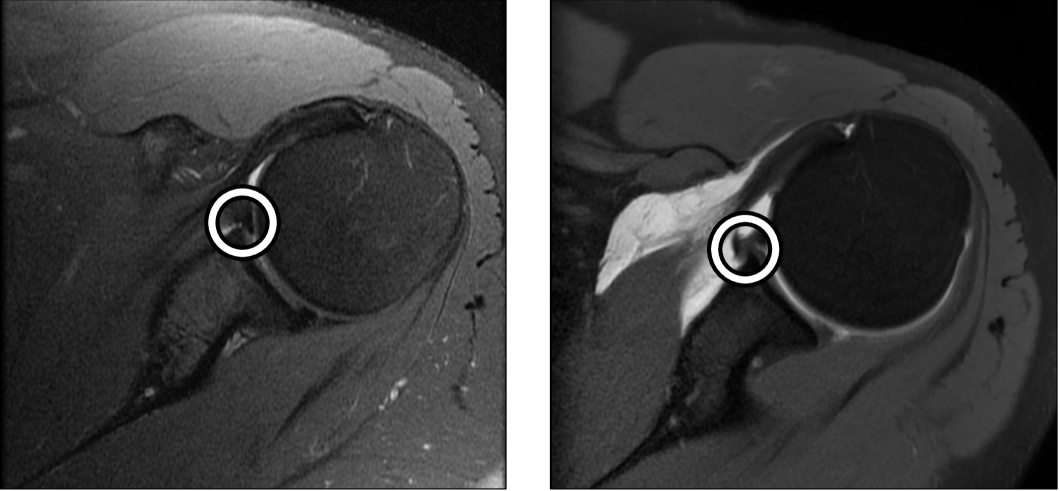

Current clinical practice often relies on MRI arthrograms (MRAs), where contrast is injected into the joint to enhance visualization of labral structures [15, 16]. The improved visualization of intra-articular structures is apparent in Fig. 1, which depicts the same Bankart lesion on an MRA and a standard (non-contrast) MRI. While MRAs achieve sensitivity and specificity rates of 74–96% and 91–98%, respectively [17, 18, 19], they are invasive, more expensive than standard MRIs, and associated with patient discomfort and risks such as allergic reactions and joint infections [20, 15, 21, 22, 23, 24]. Standard (non-contrast) MRIs, on the other hand, are non-invasive and more widely available but are significantly less reliable for detecting Bankart lesions, with reported sensitivity rates as low as 52–55% [25, 26]. This disparity underscores the urgent need for non-invasive diagnostic approaches that can match the diagnostic accuracy of MRAs while reducing patient burden and healthcare costs.

![]() |